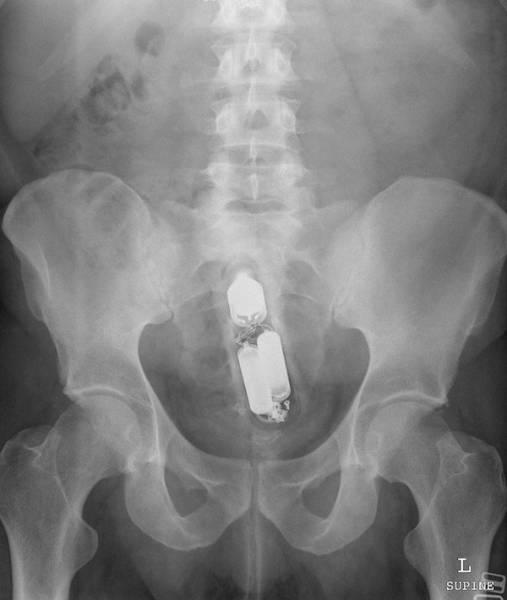

#2 Aerosolipullo (alapäästä sisään)